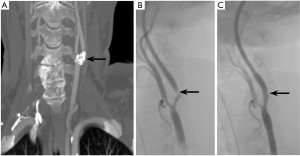

A 66-year-old female with symptomatic, severe right ICA stenosis diagnosed based on carotid DUS (PSV 150 cm/sec, ICA/CCA ratio of 3.6) and confirmed by CTA, causing multiple episodes of right eye amaurosis fugax. Comorbidities included moderate-severe CHF, CAD status post coronary stenting, prior smoking, obesity, hyperlipidemia, diabetes mellitus type 2 and CKD stage 3b. The lesion was circumferentially calcified, and the patient underwent trans-carotid stenting with shockwave lithotripsy and angioplasty balloon. The TCAR was conducted in a standard fashion under general anesthesia. Once the 8Fr sheath was in place, an intraoperative angiogram confirmed good placement of the delivery sheath and demonstrated a 30 mm long, severely calcified, 95% stenosis of the ICA (Figure 3A). Under roadmap assistance, a 0.014 wire was advanced beyond the lesion. The lesion was pre-dilated with a 5.5 mm × 60 mm shockwave angioplasty balloon (unknown number of cycles; Figure 3B), followed by stenting with an 8 mm × 40 mm Precise stent. The stent was post-ballooned with a 6 mm balloon. Flow reversal was then allowed for 2 min. Completion angiogram showed complete expansion of the stent with no residual stenosis, dissection, or contrast extravasation (Figure 3C). Total flow reversal time was 25 minutes. At 10-month follow-up, the patient remained neurologically intact, and the right ICA stent was widely patent on US (PSV 75 cm/sec, ICA/CCA ratio of 1.7).